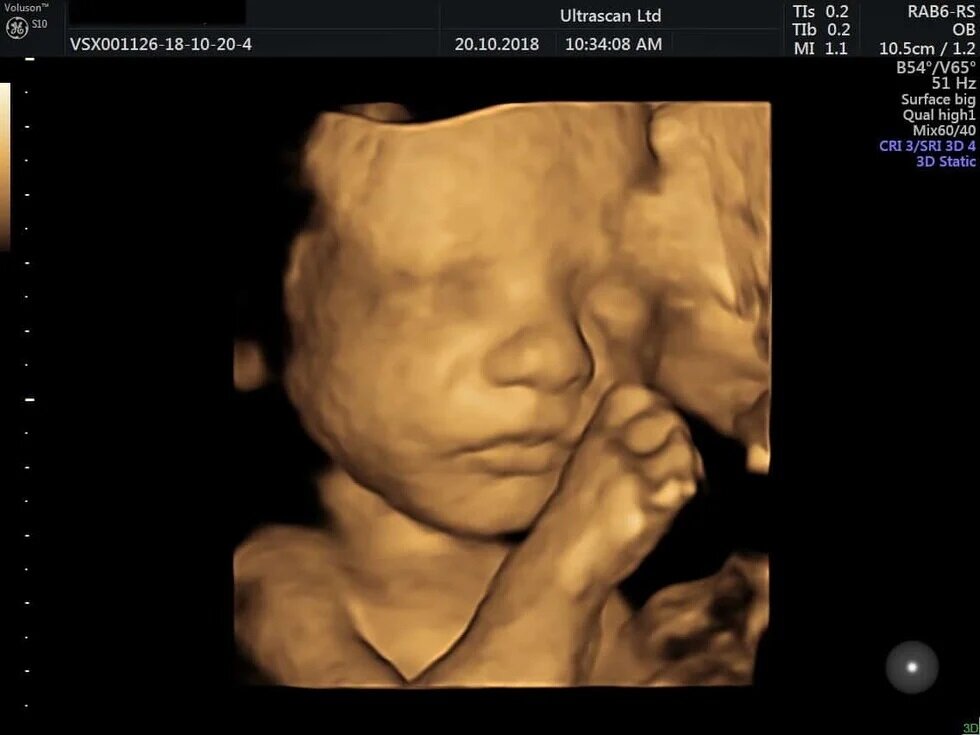

Οι 2D εικόνες δείχνουν έμβρυα να χαμογελούν με τα καρότα και σχεδόν να κλαίνε με τη λαχανίδα

Αφού περίμεναν 20 λεπτά μετά την κατανάλωση, οι γυναίκες υποβλήθηκαν σε 4D υπερηχογραφήματα, τα οποία συγκρίθηκαν με 2D εικόνες των εμβρύων.

Το τράβηγμα της γωνίας των χειλιών, που υποδηλώνει χαμόγελο ή γέλιο, ήταν σημαντικά υψηλότερο στην ομάδα του καρότου σε σύγκριση με την ομάδα της λαχανίδας και την ομάδα ελέγχου. Ενώ κινήσεις όπως η ανύψωση του άνω χείλους, η ρίψη του κάτω χείλους προς τα κάτω, το πάτημα των χειλιών και ένας συνδυασμός αυτών – που υποδηλώνει ένα πρόσωπο που κλαίει – ήταν πολύ πιο συχνές στην ομάδα της λαχανίδας σε σχέση με τις άλλες ομάδες.